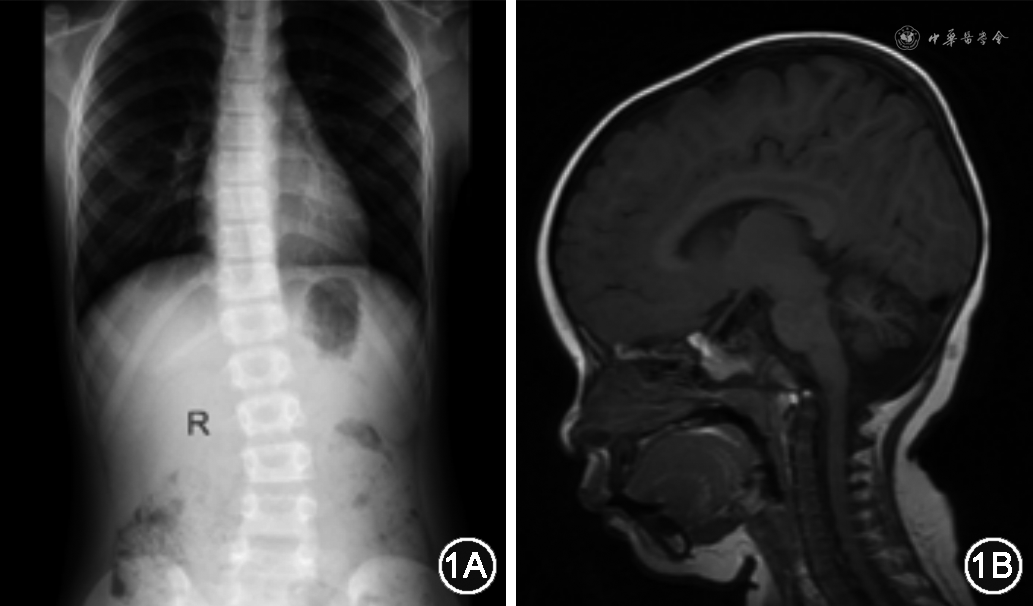

实验室检查:肝功能检查未见发现天冬氨酸转氨酶、丙氨酸转氨酶升高以及碱性磷酸酶异常;肾功能未见异常;免疫球蛋白水平未见异常。心脏超声未见明显异常。脊柱X光片提示脊柱侧弯(Th5-L2段);头颅MRI可见小脑发育不良,见图1。Gesell儿童发育测试:适应性36分,大运动40分,精细动作33分,个人社交43分。